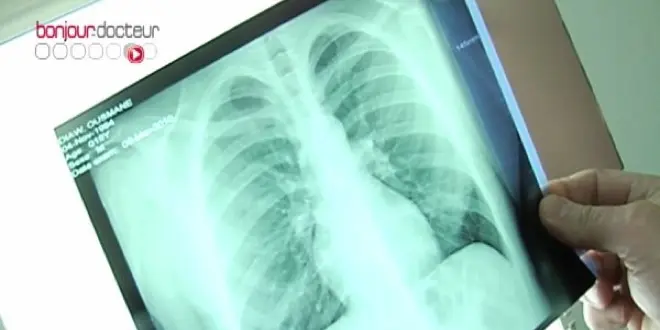

Le germe tuberculeux est une bactérie : le bacille de Koch (Mycobacterium tuberculosis). Dans plus de deux tiers des cas, l’infection touche les alvéoles pulmonaires, sites des échanges respiratoires[1]. Le bacille va se multiplier à l'intérieur des cellules de défense des alvéoles (les macrophages alvéolaires), puis progressivement attaquer l’ensemble du tissu pulmonaire. La personne a des difficultés respiratoires, une toux persistante, un épuisement chronique, une perte de poids et d'appétit ou encore des sécrétions contenant du sang.